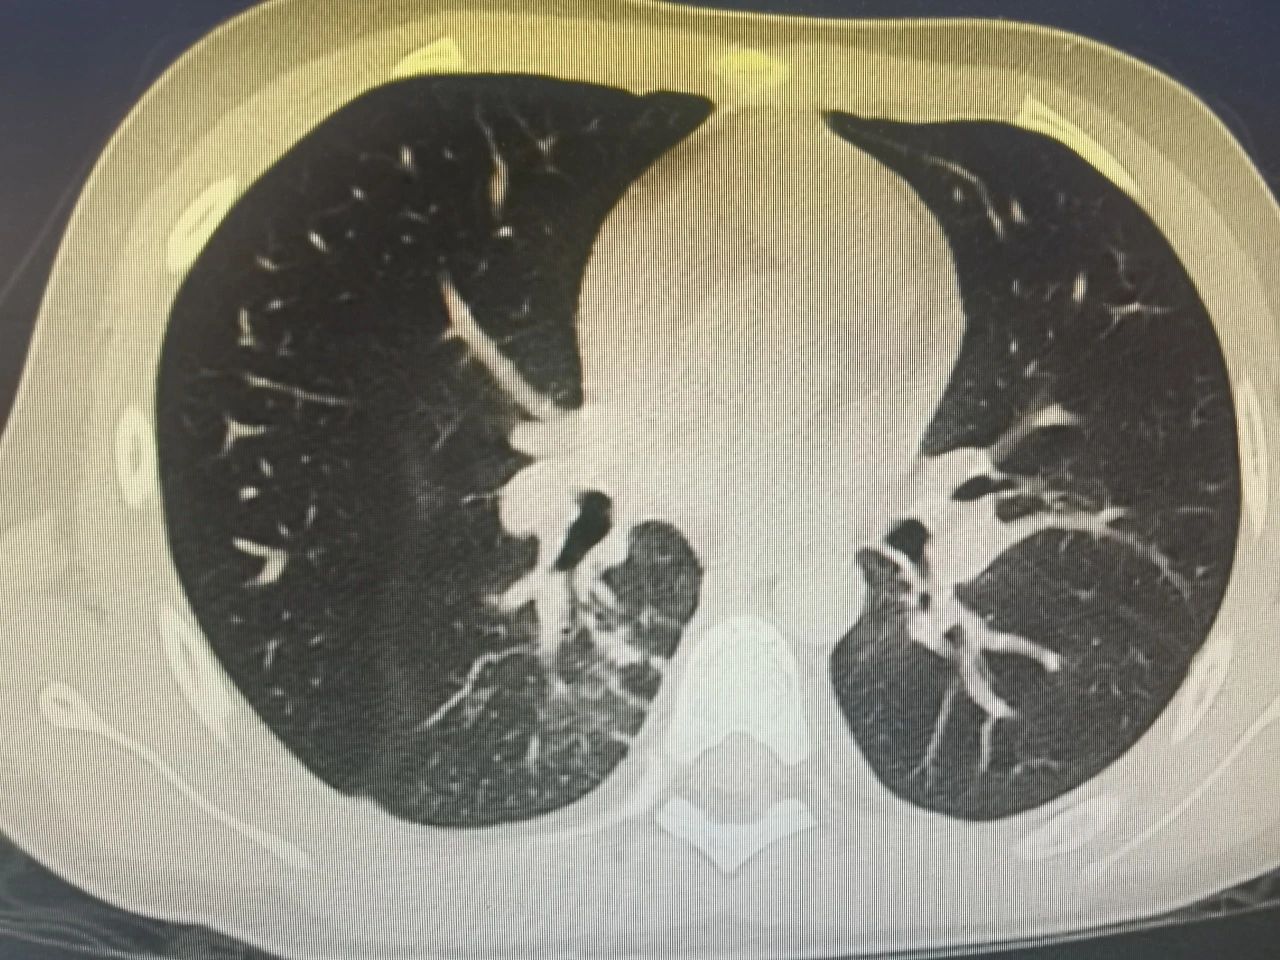

半个多月前,一名9岁的小男孩七七在父母的陪伴下,来到了锦州市妇婴医院(妇幼保健院)小儿呼吸科。因为反复高热、咳嗽10天,辗转于外院治疗6天,病情却逐渐加重,反复39-40度不退,复查的肺CT提示重症肺炎。

节假日期间,七七出现了间歇性胸痛,疼出了眼泪,又出现了一次低热,家属的心再一次提到了嗓子眼儿。刘铁英主任连忙赶到医院看望他,担心重症肺炎可能出现恢复期的肺栓塞,又紧急联系放射线,放射线曹主任马上安排会诊给他急查了肺增强CT。结果出来后没有发生栓塞,医护人员和家属都松了一口气,考虑跟胸水吸收后引起的胸膜牵扯痛有关系,对症处置后2-3天胸痛消失,发热也很快消失。